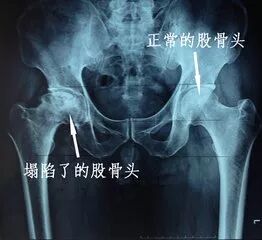

股骨头坏死是一种常见而难治的严重骨科疾病,作为骨科疾病中最难治愈的一种疾病,股骨头坏死有其自己的发展过程。从影响股骨头血运开始。髋部外伤、使用激素类药物、大量饮酒、风湿、类风湿、骨质疏松血液系统疾病等因素在人体中似一颗"定时炸弹",可能随时引发股骨头坏死,这是股骨头坏死发生的前提,有过以上经历的人,会严重损伤和堵塞股骨头及其附近血管,阻碍体内正常的血液循环,使股骨头骨组织不断缺血,日积月累,坏死骨区不断扩大,各组织再生能力下降,坏死形成。但可以将这些致病原因进行细致的分析为创伤性和非创伤性两种。创伤性股骨头坏死的原因是外界影响,如因意外的摔倒、撞伤、扭伤等情况,造成股骨颈骨折、髋关节脱位、髋臼骨折和粗隆间骨折等髋部外伤,破坏了损伤部位的血管,影响到股骨头的血供,导致股骨头缺血坏死。

股骨头坏死理想的治疗应该为:既能保留自身的股骨头,使其坏死部分能够大部分修复,又能较快的消除疼痛症状,改善髋关节的功能,并且使发疾病得到有效治疗和控制。我院长期从事此类疾病的治疗和研究,针对股骨头坏死这一疾病提出了全新的观念,我们认为髋关节周围软组织由于慢性损伤或急性外伤后以及强直性脊柱炎、类风湿性关节炎等原因引起髋部软组织慢性无菌性炎症病变,导致臀腿部软组织广泛而持久的肌痉挛并出现严重疼痛,股骨头生物力学失去平衡,股骨头在持续过强的肌肉拉紧的压迫作用下,髋关节内压力增高,软骨面受损,骨质出现坏死性病变,同时疼痛引起髋部血供不良,加重了股骨头坏死,股骨头变形,出现脱位或半脱位,长期髋部供血严重不良、股骨头重度受压者,甚至可导致股骨头完全坏死溶解消失。髋关节可出现内收、前屈和外旋畸形、患肢缩短(2cm以上),行走可有明显跛行。  基于对股骨头坏死的深入研究,针对股骨头坏死的病理情况,我院在长期的临床实践中,设计了一系列术式,通过髋关节周围软组织松解术,从根本上消除了髋部软组织的痉挛及慢性炎症,恢复了股骨头的生物力学平衡,明显改善了股骨头的血循环,在短时间内,迅速消除髋部疼痛,改善髋关节功能,恢复中期(半年至一年以上),绝大部分患者坏死的股骨头,骨质坏死部分骨密度增强,骨小梁形成,坏死区域明显缩小或消失,坏死部分能自行修复,股骨头成活,保留了自身的股骨头,恢复长期(2—3年以上),股骨头自我修复结束,受力稳定,可离拐行走,跛行步态大部分得到纠正。